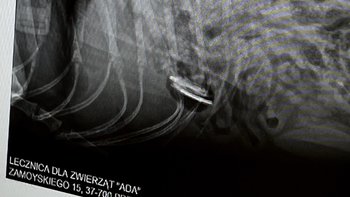

Trzy metalowe śruty tkwią w ciele Draco. Trzy metalowe dowody na to, że ktoś uznał, że jego życie jest nic nie war…